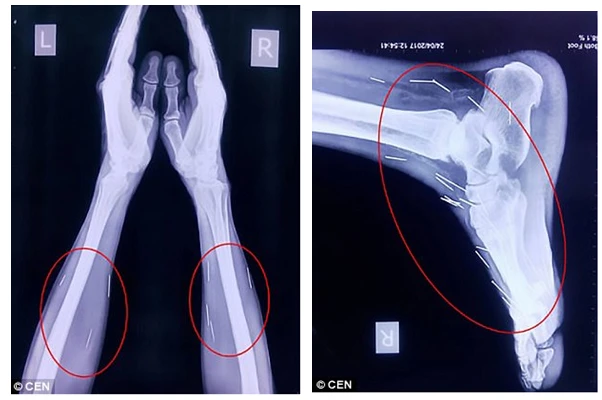

Chân và tay bệnh nhân cũng có hàng chục cây kim khác. Ảnh: DAILY MAIL

Sau khi tiếp tục kiểm tra, các bác sĩ phát hiện có tới 75 cây kim trong cơ thể ông Meena. Trong số 75 cây kim, có 40 cây nằm trong cổ họng, 25 cây ở chân và 2 cây ở cánh tay.